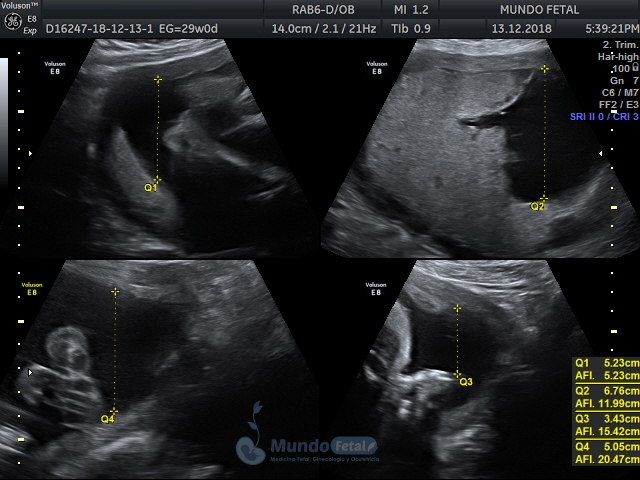

Mediante esta técnica ultrasonográfica, evaluamos en tiempo real al bebe y monitoreamos electrónicamente la frecuencia cardiaca fetal, vigilando los siguientes parámetros:

A cada parámetro se le asigna un puntaje basado en una escala del 0 al 10. Se ha propuesto que en estados fetales alterados por disminución del oxígeno se alteran los parámetros de manera que podemos predecir el estado fetal evaluando estos puntos.